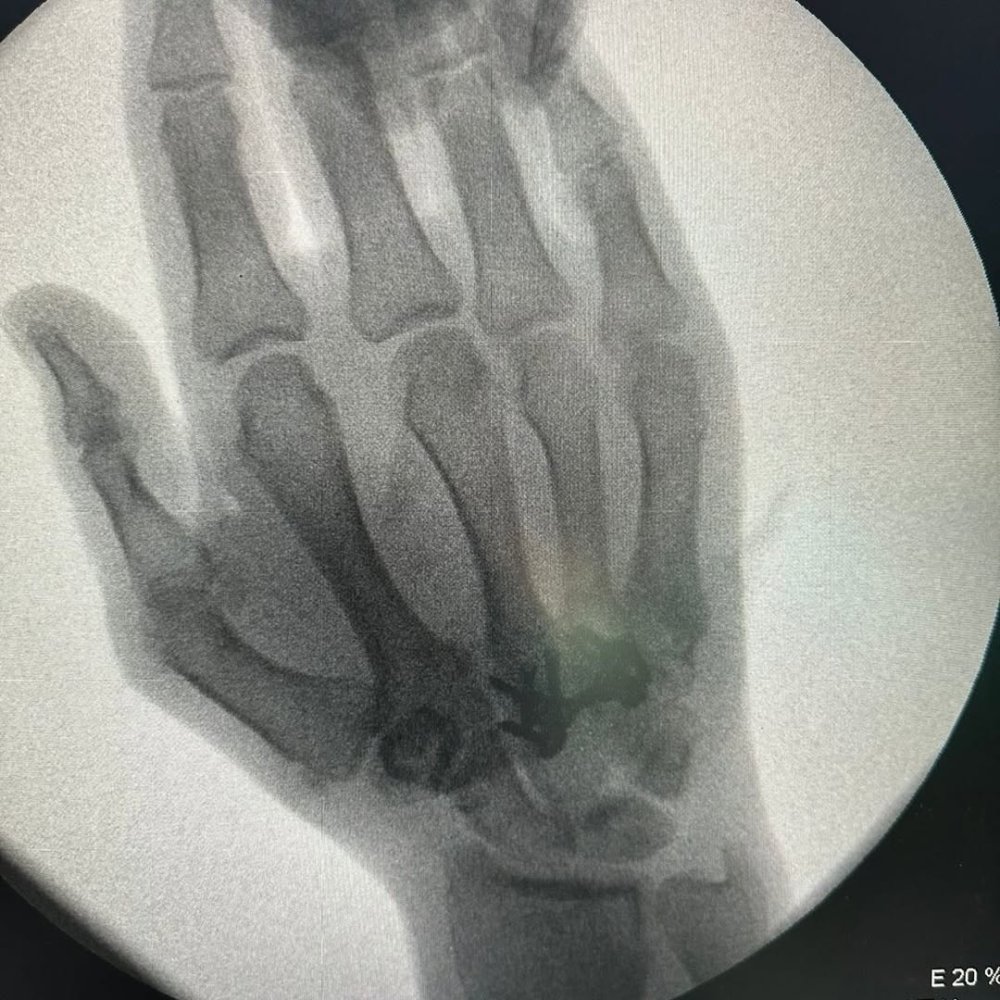

Prosport.Az-ın xəbərinə görə, 40 yaşlı idmançı həm burnundakı çəpər əyriliyindən, həm də sol əlindəki 3 qırıq sümüyə görə həkim bıçağı altına yatıb.

Hər iki əməliyyat uğurla keçib.